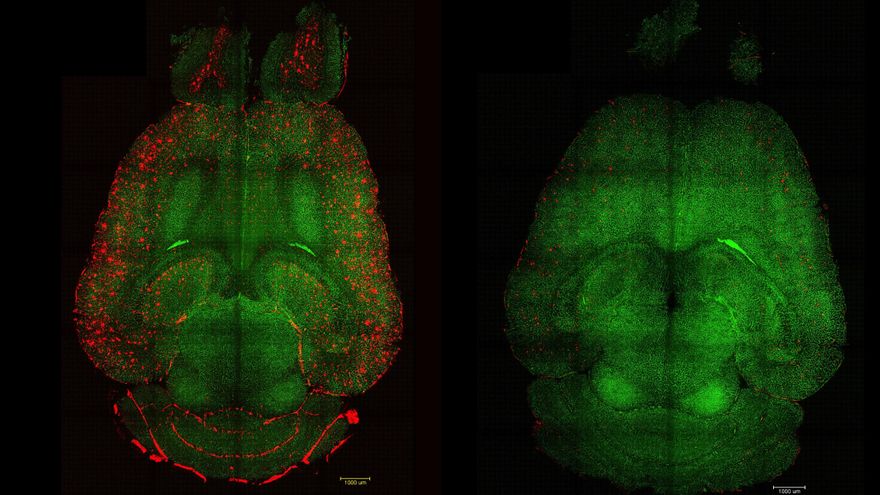

Utilizaron una prueba no invasiva que mide la actividad metabólica del cuerpo humano en tiempo real (Tomografía por Emisión de Positrones, PET) para medir los niveles basales de Beta-amiloide en las placas y de Tau en los ovillos neurofibrilares del cerebro de los participantes. Paralelamente, midieron la actividad física de los participantes con podómetros de cintura.

Los participantes se sometieron a evaluaciones cognitivas de seguimiento anual durante un periodo de entre 2 y 14 años (una media de 9,3 años), y un subgrupo se sometió a también pruebas PET para analizar los cambios en la proteína Tau. Los resultados mostraron que un mayor número de pasos se relacionó con tasas más lentas de deterioro cognitivo y una acumulación más lenta de proteínas Tau en los participantes con niveles basales elevados de proteína Beta-amiloide.

El ejercicio, por tanto, provoca que la acumulación de la proteína Tau sea más lenta, y la falta del mismo tiene el efecto contrario. “Nuestro estudio demuestra que cada paso cuenta, e incluso un aumento pequeño de actividad redunda en una mejora de la salud cerebral y cognitiva. Mantenerse físicamente activo es una forma de proteger el cerebro”, señala otra de las autoras, Wai-Ying Wendy Yau, neuróloga del Mass General Brigham, en un comunicado del centro.